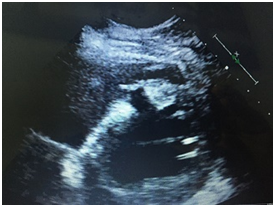

Coronary angiogram also showed 3 coronary vessel disease occluded mid LAD by thrombus at bifurcation with large diagonal so recanalized and stented LAD and postdilated properly. LV gram showed large ventricular septal defect VSD 14 x10 mm in anterior septal wall with tunal shape associated with significant left to right shunt (Figure 2A & 2B).